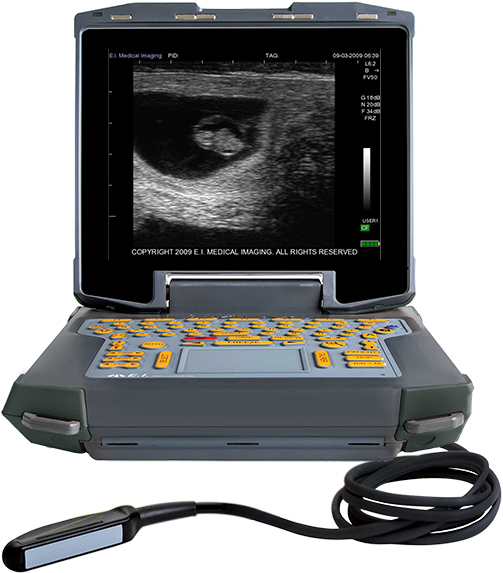

牛用B超机测孕

牛用B超机在种畜牛肉养殖场中越来越受到欢迎,因为牛用B超机可用于早期妊娠检测和胎儿公母确定。牛用B超机可以在配种后26天左右进行早期妊娠检测,而需要测公母则要在60~90天进行。有些人使用小母牛的胎儿公母作为根据风险对怀孕小母牛进行分类,怀有公牛犊的小母牛可能是对于较大的小腿尺寸,更有可能有困难。在大型牛群中,这允许用于加强对一小群小母牛的监测。

与触诊一样,当时可以检测到生殖道问题的检查。超声波还可以检测胎儿心跳以确认可行性。超声检查可以以与触诊和新触诊大致相同的速度进行。“无臂”超声装置通过放置探头来减少触诊器的磨损在插入的延长臂的末端,不需要手动操作的探针。超声检查通常与人均略高有关触诊充电。